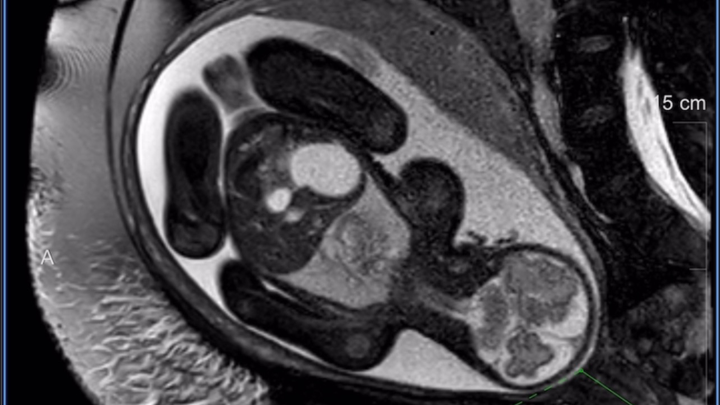

Hi, I’m Jack, and my amazing wife Alicia is now 31 weeks pregnant with our daughter, Sophia Grace. What started as a joyful ultrasound visit, so Alicia’s mom (visiting from California) could see her grandbaby, turned into an unexpected diagnosis at 27 weeks: duodenal atresia, a blockage in Sophia’s small intestine (the “double bubble” sign on MRI).

The great news? Our detailed fetal MRI at Cincinnati Children’s confirmed everything else is perfect; heart, lungs, brain, eyes, spleen, limbs, and strong growth. Genetic testing came back low risk for Down syndrome and other conditions. Sophia is a fighter, and we’re so grateful.